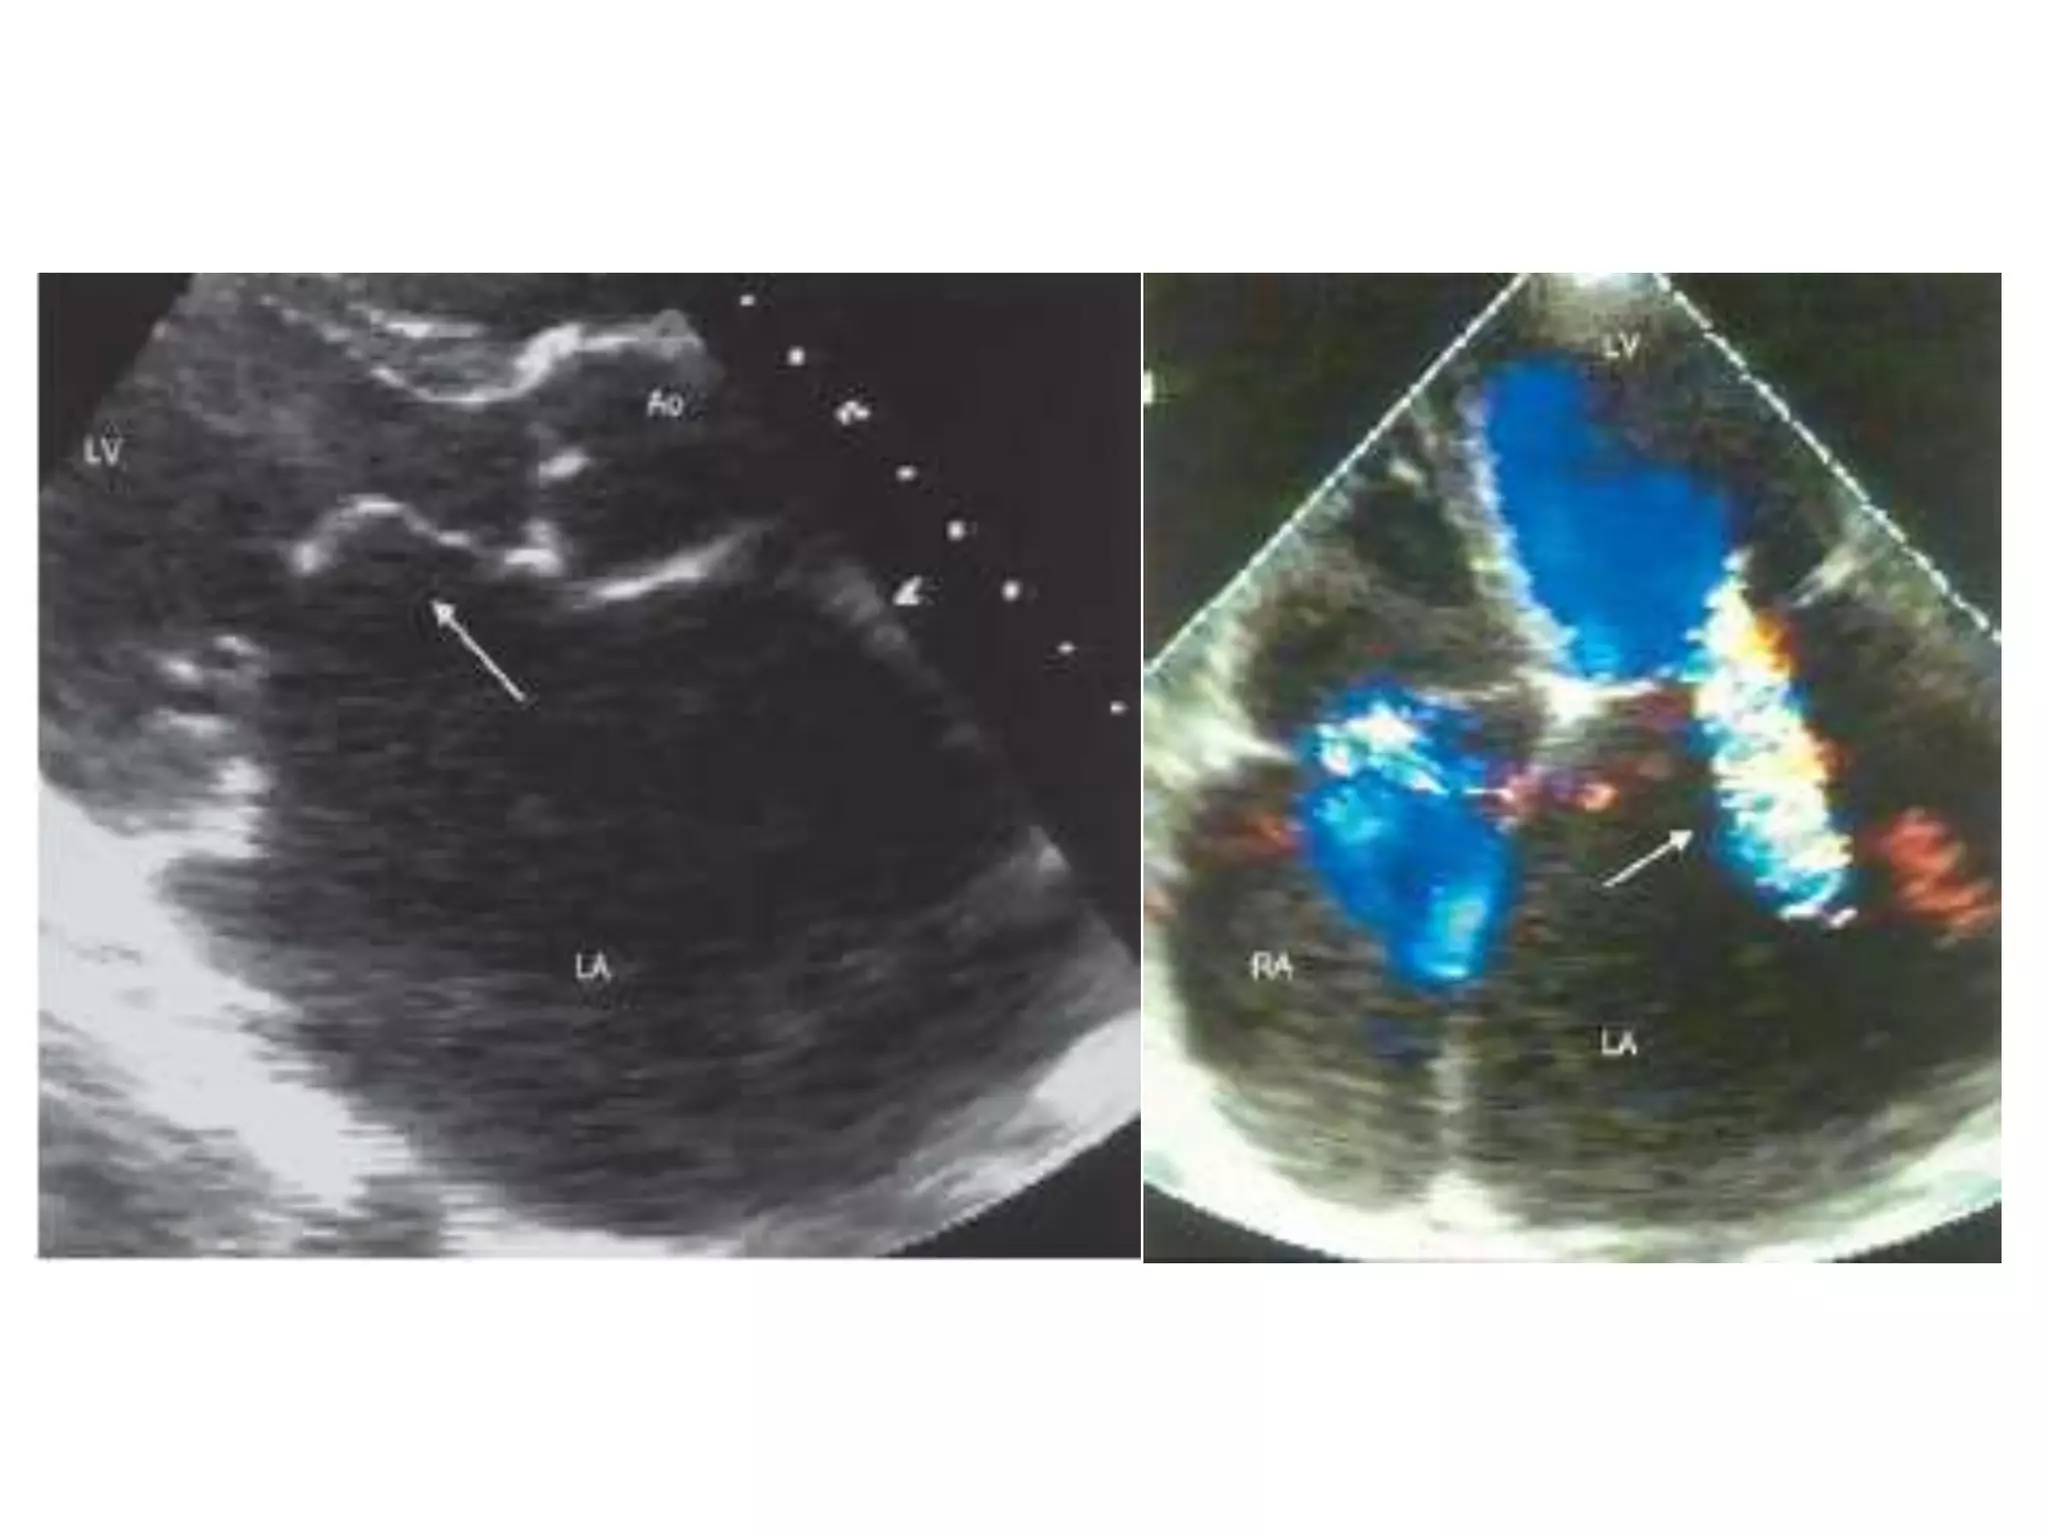

VSD